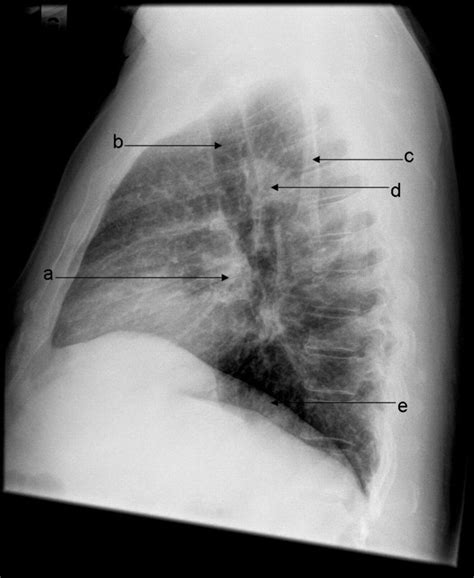

Interpreting a Lateral Chest X Ray requires a trained eye and knowledge of normal anatomy. Key structures to assess include:

• The heart and its borders

• The lungs and any visible abnormalities

• The diaphragm and its position

• The ribs and spine

• lateral chest x ray labeled